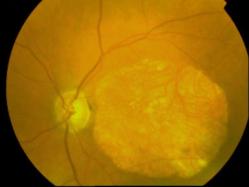

CICATRICE APRES EXERESE CHIRURGICALE DE NEOVAISSEAUX

IM000007.JPG